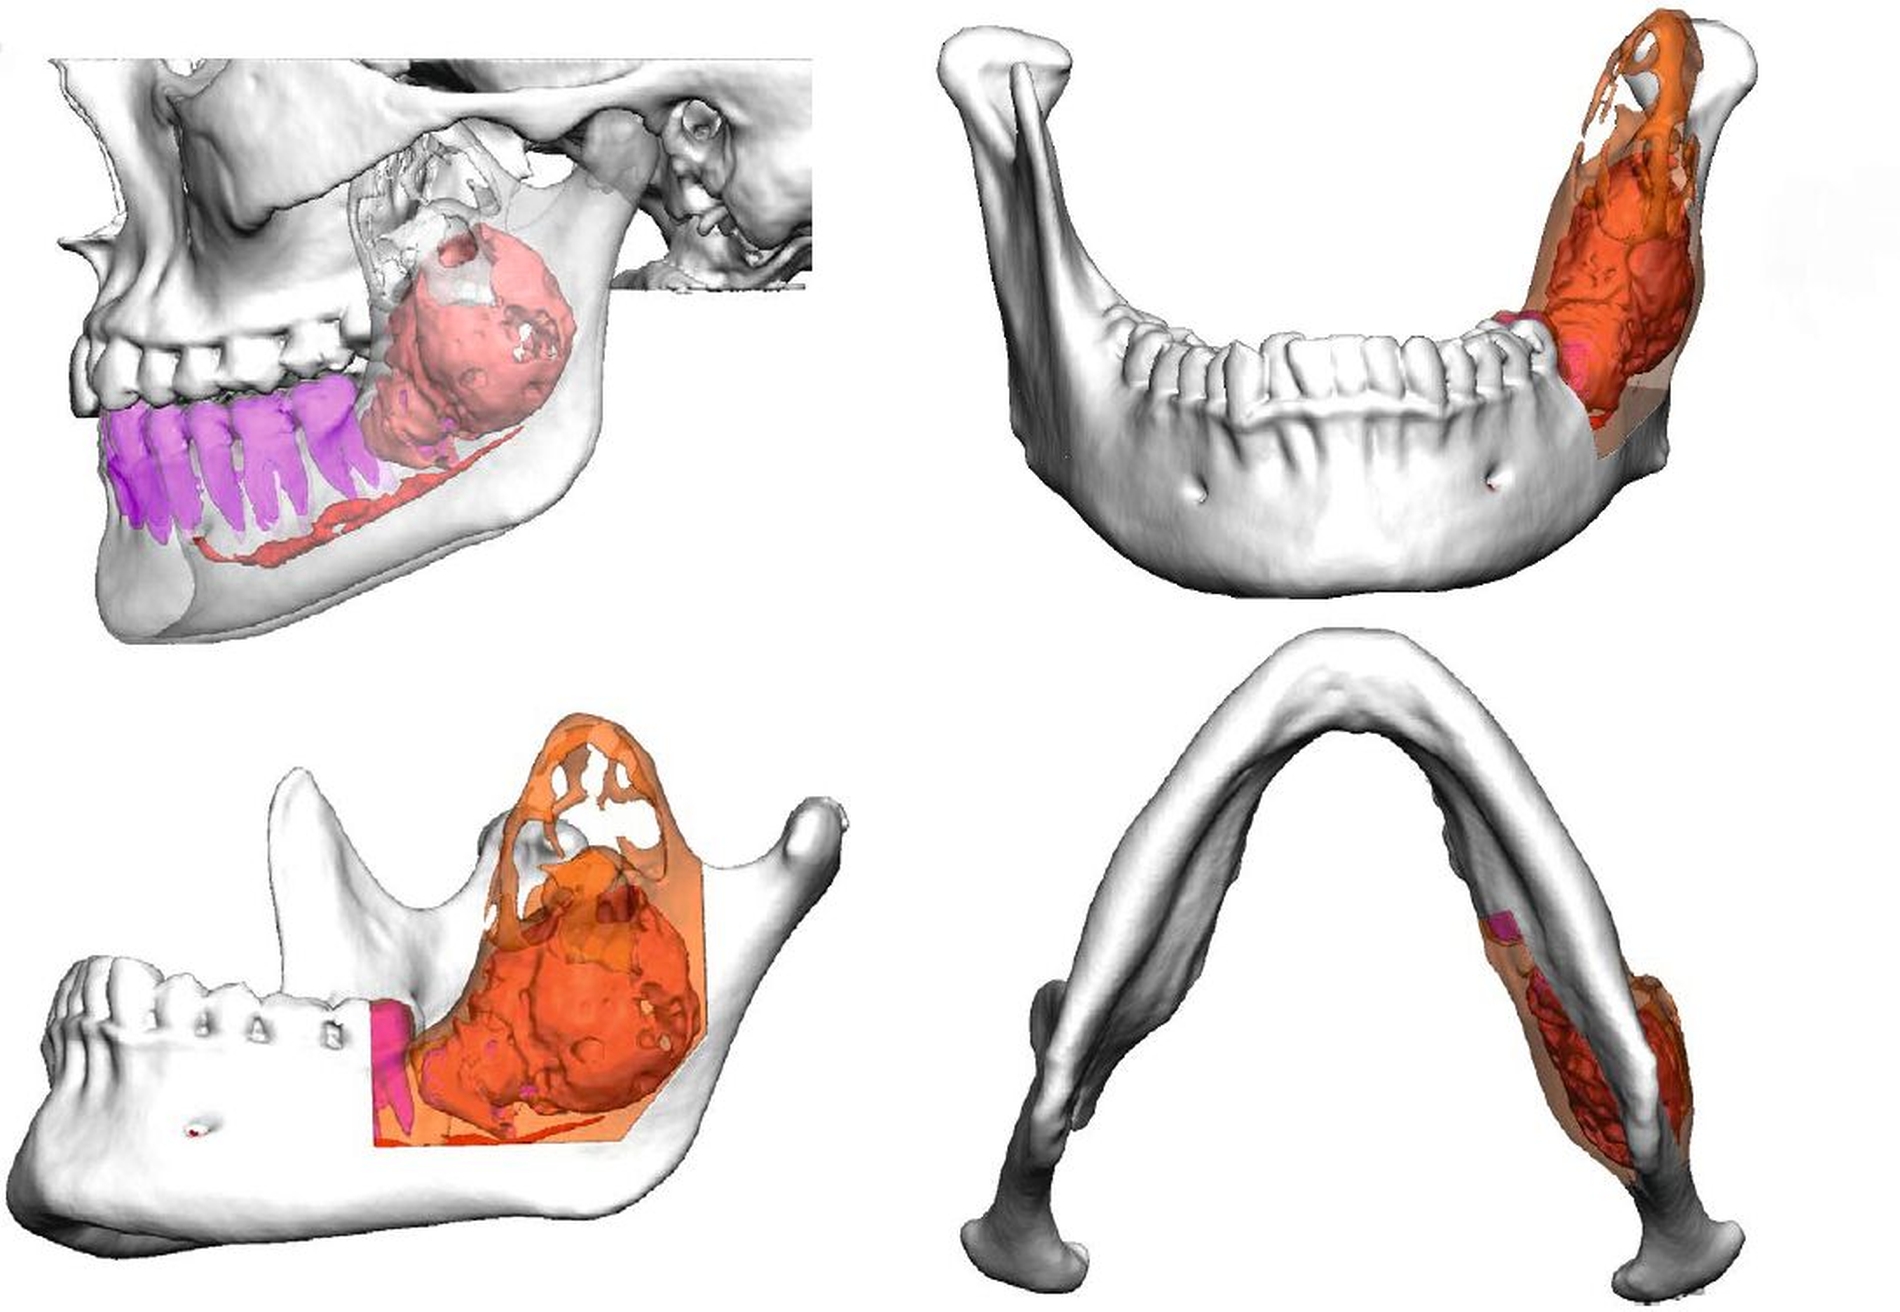

Die Therapie der Wahl bei Odontomen stellt die Enukleation dar. Aufgrund der Ausdehnung der Raumforderung und der Nähe zum N. alveolaris inf. entschieden wir uns dazu, eine 3-D-virtuelle Operationsplanung durchzuführen. Anhand des zuvor angefertigten Computertomogramms erstellten wir eine Resektionsschablone im CAD/CAM-Verfahren, um so eine Kontinuitätserhaltung zu garantieren. Weiterhin erfolgte die CAD/CAM-Fertigung einer Rekonstruktionsosteosyntheseplatte (Abbildungen 2 bis 4).

Die computerassistierte Chirurgie ermöglicht eine präzise, 3-D-unterstützte Operationsplanung und kann im Fall von ausgedehnten Befunden eine vorhersagbar durchzuführende Operation ermöglichen. Im vorliegenden Fall konnte das Ausmaß der Resektion auf ein Minimum beschränkt werden; somit konnten sowohl die Unterkieferkontinuität als auch die Sensibilität des N. alveolaris inf. erhalten werden.

Durch die Anfertigung einer CAD/CAM-gefertigten Rekonstruktionsplatte kann eine ideale Positionierung und Passung des Osteosynthesematerials garantiert werden, was die Operationszeit verkürzen und postoperativen Komplikationen, zum Beispiel einer Plattenexposition, durch mangelhafte Passung entgegenwirken kann.